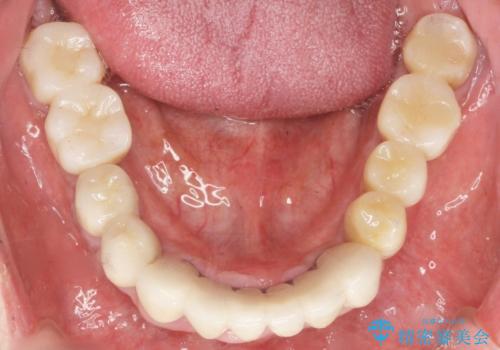

歯がぐらぐらで咬めない 奥歯のインプラント 50代男性

- 奥歯がぐらぐらで咬めないことを主訴に来院された患者様です。

仕事が忙しくなかなか自分のことに気が回らなかったそうですが、どんどん歯の動揺が増し「もう限界だ!」と思い受診を決断したとのことでした。

精査したところ、全顎的な重度の歯周病により左下のブリッジ(左下④56⑦)の著しい動揺を認めました。

禁煙指導と歯周病治療後、左下臼歯部(左下467埋入)のインプラント治療を行いました。

奥歯で咬むことができるようになり、喜んで頂けました。

治療終了後には「なんでも食べられるようにしてくれてありがとうございます!」とおっしゃって下さいました。